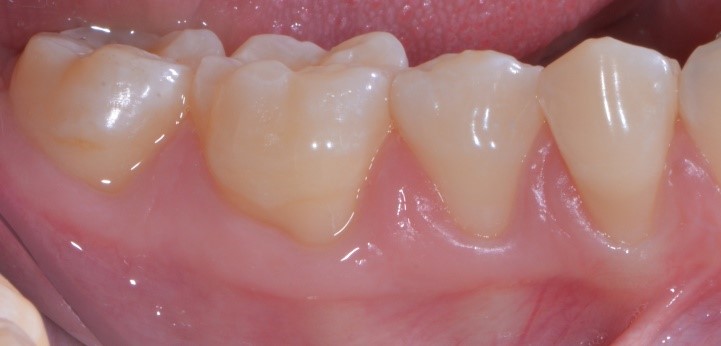

Vediamo il caso iniziale. Francesca presentava recessioni multiple con accentuata ipersensibilità dentinale.

Perché, secondo te, Francesca ha accettato di farsi tagliuzzare in 2 punti per risolvere questo problema? Te lo spiego io: perché io sapevo di poterle dare questa guarigione a 10 giorni

e questa a sei mesi.